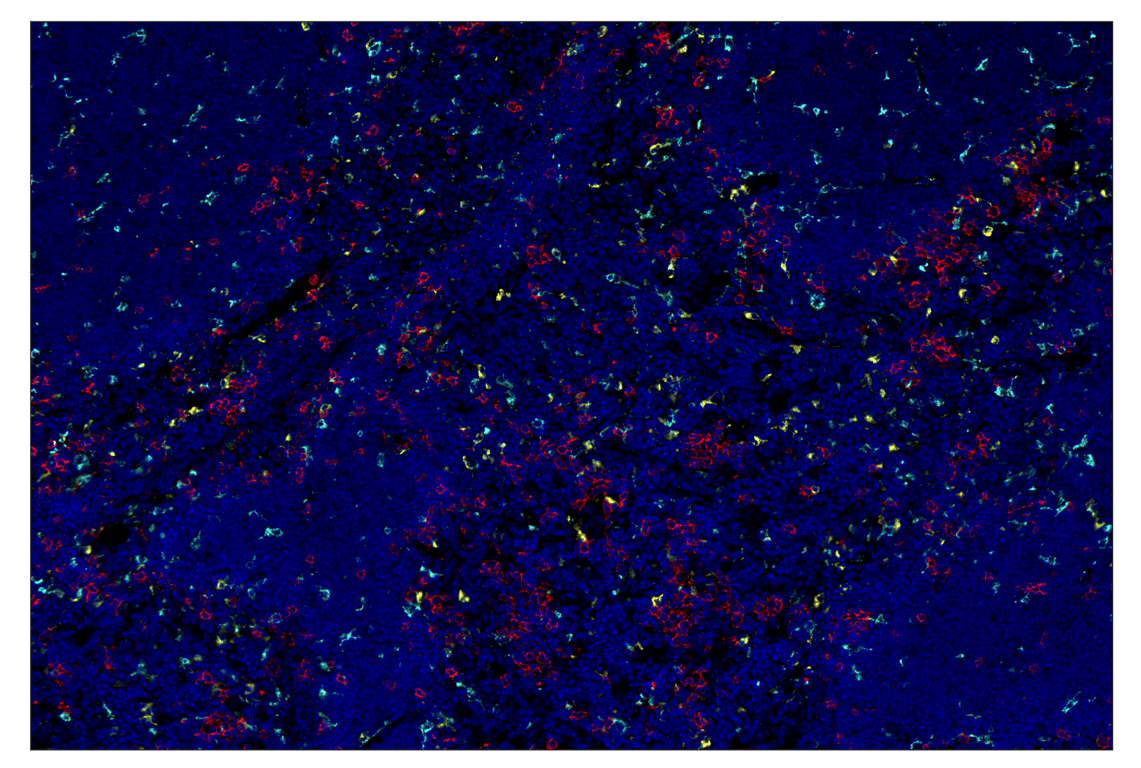

CD68 (E3O7V) & CO-0096-488 SignalStar™ Oligo-Antibody Pair #29690

SignalStar Oligo-Antibody Pairs are compatible with the SignalStar Multiplex IHC Buffer Kits for use in fluorescent multiplex imaging experiments. This product includes the oligo-conjugated antibodies and complementary oligos required for labeling your target protein on up to 10 slides. SignalStar Multiplex IHC Buffer Kits are required to amplify and image the target signal. Multiple oligo-antibody pairs can be conveniently combined into a multiplex panel using the SignalStar Multiplex IHC Panel Builder. SignalStar Multiplex IHC Kits & Reagents are not compatible with all of Cell Signaling Technology® products and protocols that are recommended for use in immunohistochemical assays.